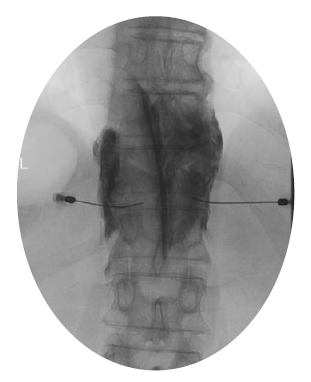

がん疼痛の治療は、世界保健機構(WHO)のガイドラインによる薬物治療を基本として行われていますが、薬物療法のみでは十分な鎮痛効果が得られないことがあります。神経ブロックは、局所麻酔薬や神経破壊薬を用いて神経の興奮を抑制することにより、鎮痛効果を発揮する方法です。当院では、ペインクリニックと連携して、がん疼痛に対する神経ブロックを行っています。